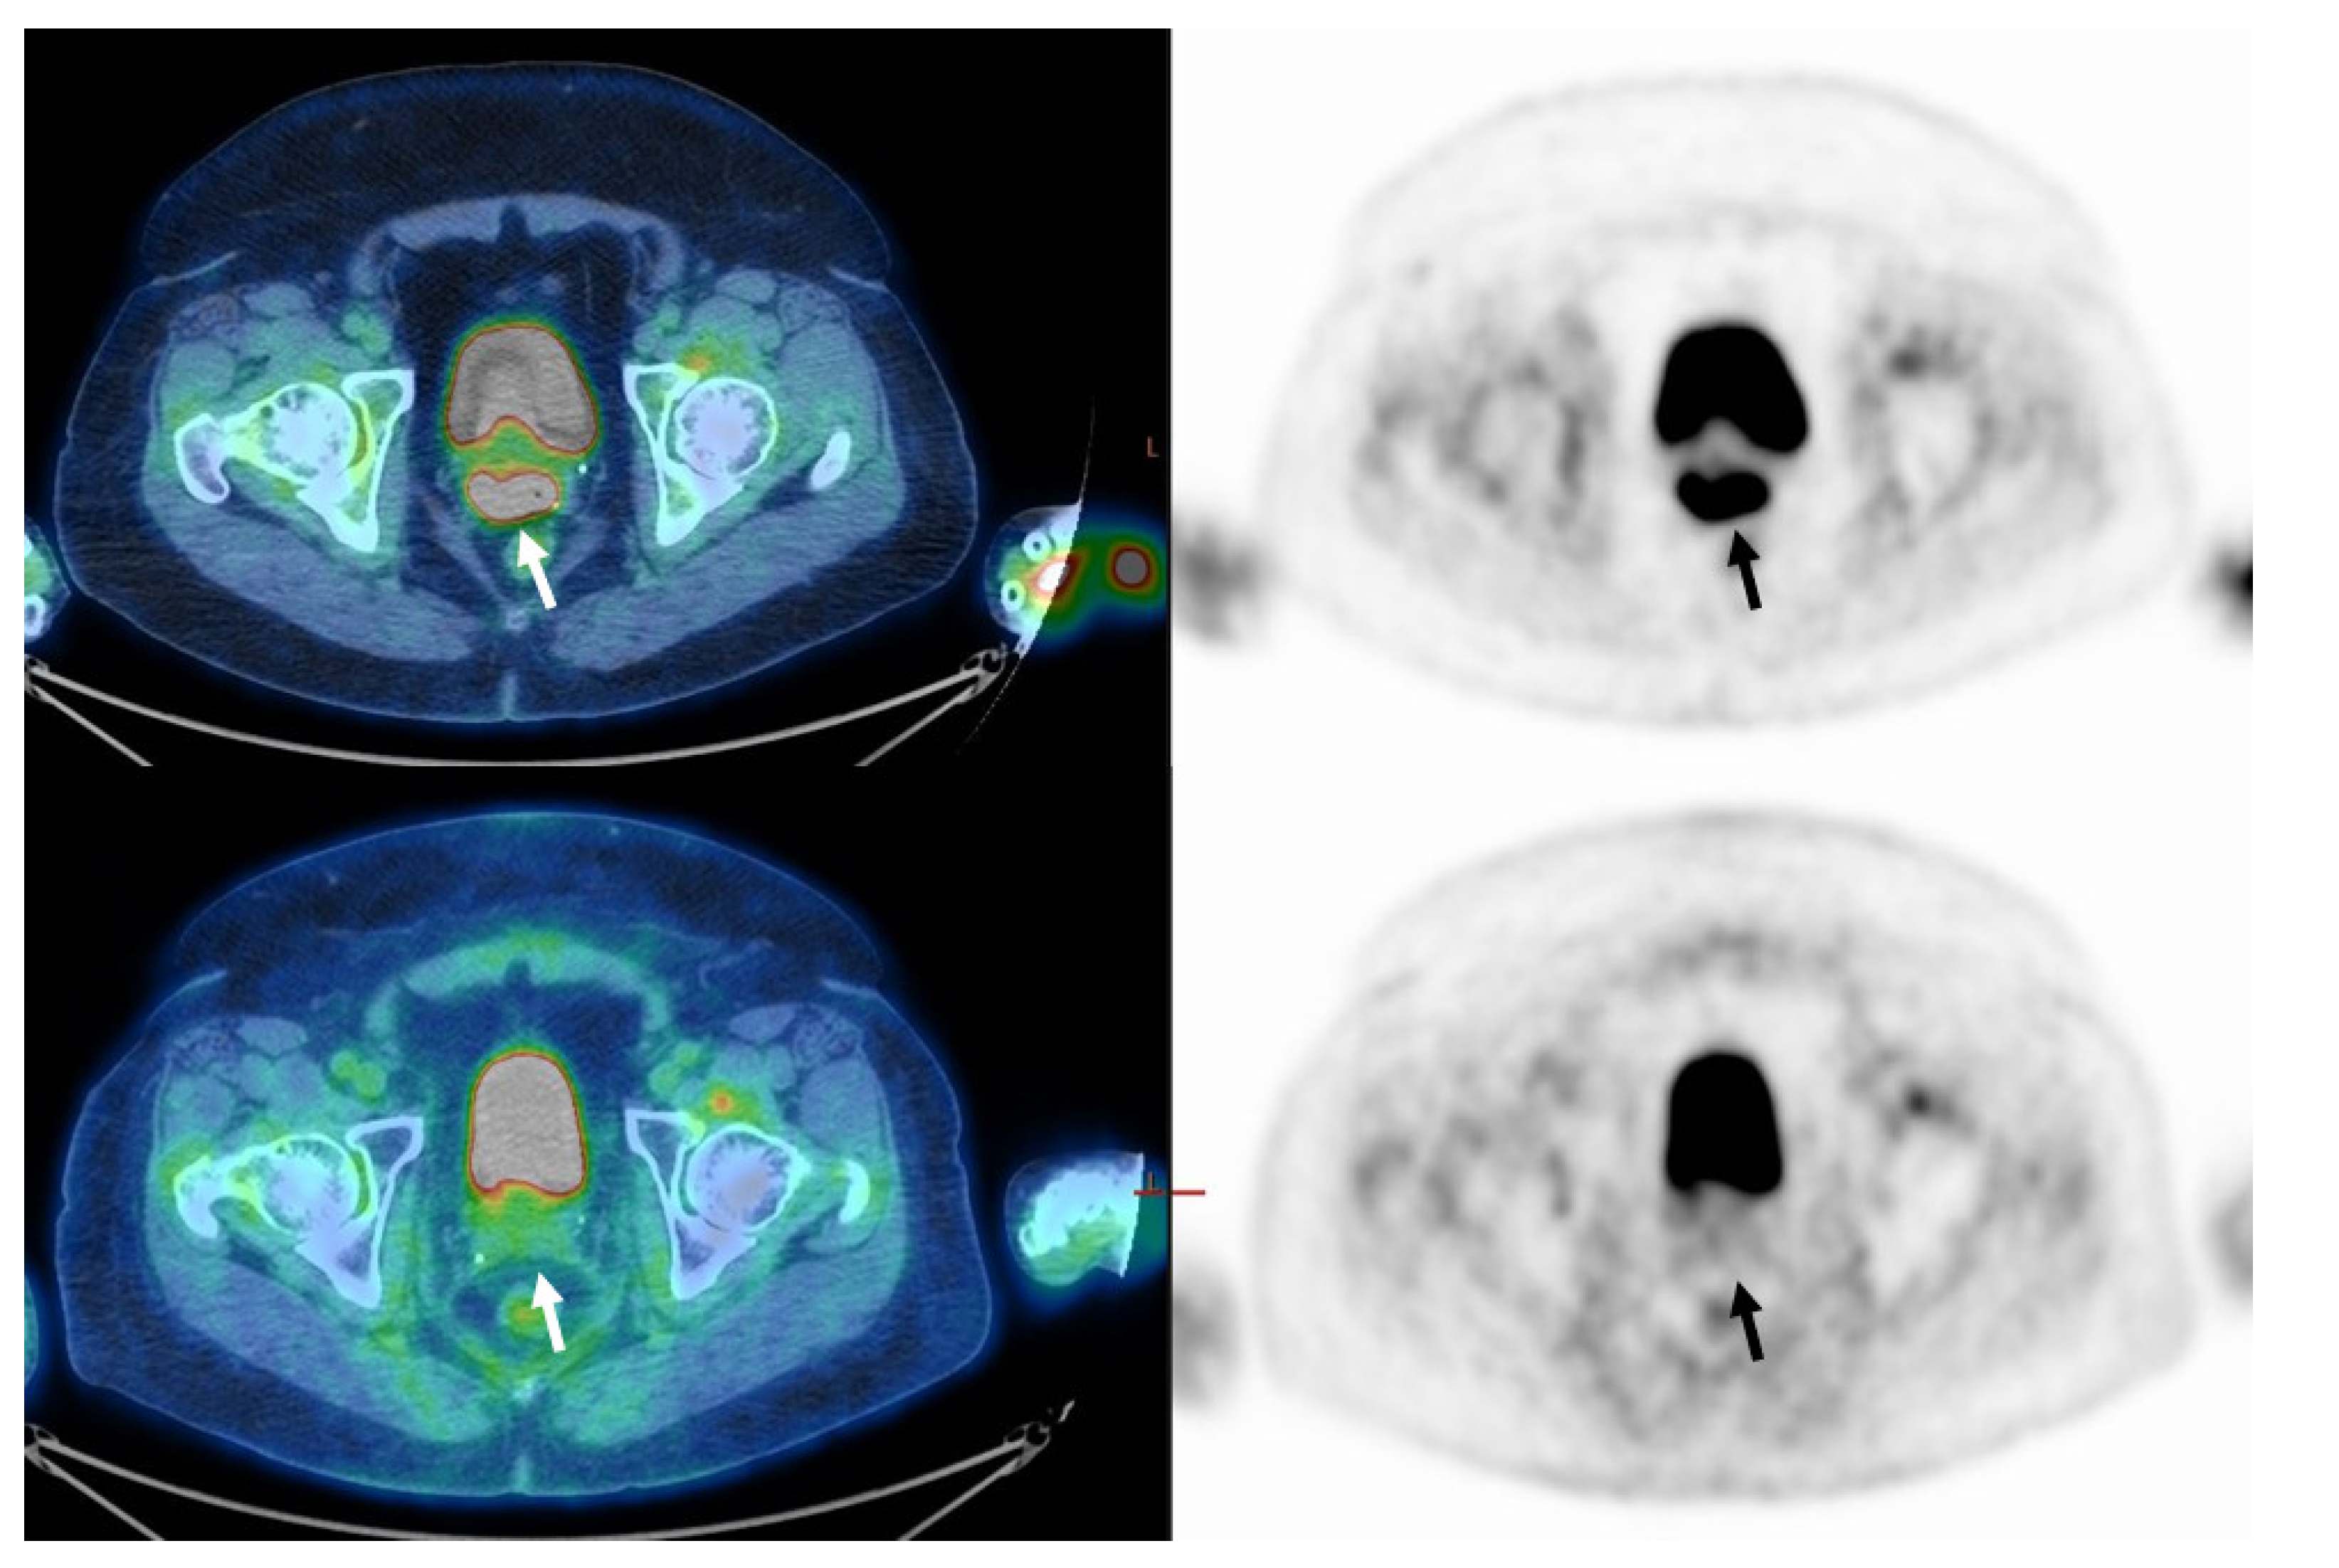

Figure 2. Seventy-year-old woman with FIGO stage IIB disease cervical cancer (Squamous cell carcinoma). On staging, PET/CT images (upper row) demonstrate pathological uptake in the primary tumor only (arrow). MTV was 85.0 cm3, and TLG 1411.2. On PET/CT performed about 3 months after the end of treatment (lower row), there is still pathological FDG uptake in the primary tumor (n-CMR, arrow). In addition, a new pathological lymph node has appeared in the right pelvis (not shown in this figure), indicating disease progression.